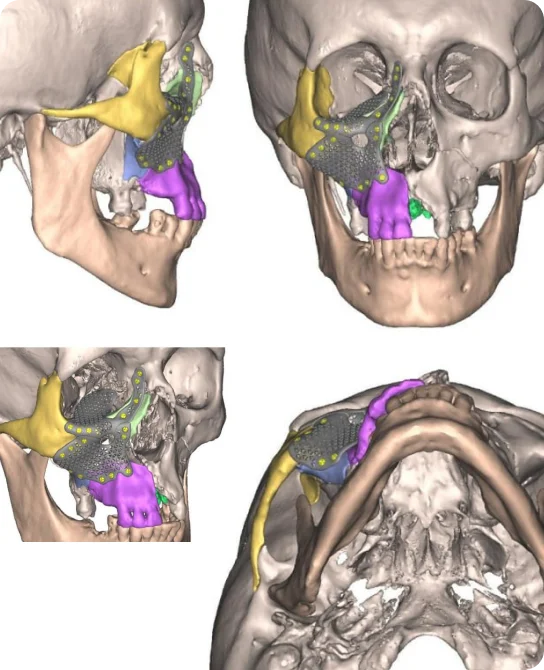

Ми співпрацюємо з провідними українськими ЩЛХ хірургами, біоінженерами та виробниками імплантатів з титану та PEEK. Мінно-вибухові травми обличчя і голови одні з найважчих як з медичної, так і з психологічної точки зору.

Сьогодні реконструктивна хірургія обличчя і голови офіційно не покривається державою. До того ж вона потребує виключно індивідуальних рішень, таких як 3D-друк титанових імплантатів ушкоджених кісток черепа, щелепи, обличчя.

На сьогодні, ніде у світі немає такого досвіду і таких технологій в реконструкції кісток обличчя, щелепи і голови, як в Україні після 2022 року. Світові експерти та українські фахівці постійно обмінюються досвідом і вдосконалюють свої навички, імплементують інноваційні методики.